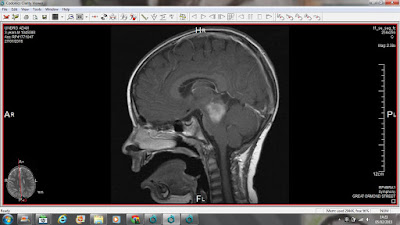

13.05.2015 dzień rezonansu...

11.10.2014-rezonans a po nim pierwsza operacja.

Wodogłowie obturacyjne spowodowane uciskiem masy guza na półkule, obrzęk mózgu. W celu odprowadzenia płynu mózgowo-rdzeniowego nie implantowano układu zastawkowowego ale zastosowano nowoczesną metodę endoskopowej wentrikulocysternostomii polegająca na wykonaniu "skrótu" dla płynu mózgowo-rdzeniowego pomiędzy komorą trzecią i przestrzeniami podpajęczymi mózgu. Po kraniektomii usunięta część czaszki, nie została umieszczona z powrotem.

szczęśliwy...wynik rezonansu wskazał na sukces drugiej operacji ( 15.10.14.) gdzie wycięto ok 60 % guza, zostawiając reszte wrastającą w pień mózgu- nieoperacyjną

27.01.2015

Progresja guza

wzrost w stronę wzgórza, możdżku i mostu pnia mózgu, widoczny ucisk na prawą półkulę. Guz ma ponad 2 cm...

13.05.2015